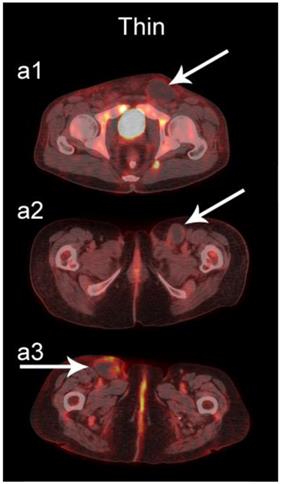

The readers scored the SP of the STSs and BFs on the 4-point avidity scale (Fig. 1). Reader agreement was substantial (κ = 0. 61) and varied among the different SPs, being highest for the thin SP (κ = 0.70) and lowest for the thick SP (κ = 0.46, Table 4). Examples of SPs with 100% reader agreement are shown in Fig. 3.

Figure 3

Examples of lesions with 100% observer agreement on assessment of SP. a Thin SP a1 A 77-year-old woman with a seroma (arrow) 17 days following excisional nodal biopsy (SUVmax = 1.7). a2 A 66-year-old woman with a seroma (arrow) 3 months following excisional nodal biopsy (SUVmax = 2.0). a3 A 21-year-old man with a seroma (arrow) 10 days following excisional nodal biopsy and hydrocele repair (SUVmax = 3.9). b Moderate SP: b1 A 46-year-old man with undifferentiated sarcoma (SUVmax = 19.4). b2 A 38-year-old man with a fungal abscess (SUVmax = 11.6). b3 A 78-year-old woman with recurrent myxoid pleomorphic undifferentiated sarcoma (SUVmax = 5.9). c Thick SP: c1 A 67-year-old man with metastatic undifferentiated sarcoma (SUVmax = 6.3). c2 A 65-year-old man with pleomorphic undifferentiated sarcoma (SUVmax = 30.3). c3 A 45-year-old man with synovial sarcoma (SUVmax = 10.9). d Solid SP: d1 A54-year-old woman with rhabdomyosarcoma (SUVmax = 15.7). d2 A 43-year-old man with pleomorphic undifferentiated sarcoma (SUVmax = 2.7). d3 A 48-year-old woman with myxoid liposarcoma (SUVmax = 2.9).

The SP of STSs was more likely to be assessed as thick or solid by all readers (p<0.0001). Modeling the diagnostic efficacy of a system that classified lesions with a thick or solid SP as an STS yielded an inter-reader averaged sensitivity and specificity of 69% and 98%, respectively.

We also examined the contribution SP to the differentiation of STSs from BFs. SP has not been as extensively investigated as SUV [36-42], and may provide additional information about the biological behavior of soft-tissue lesions on 18F-FDG PET [37]. SP can be assessed qualitatively or quantitatively. Qualitative assessments of heterogeneity, degree of peripheral nodularity, and apparent peripheral thickness of lesions have been used in the past to differentiate benign from malignant lung [38] and peripheral nerve sheath [39] tumors, and to distinguish between high-grade and low-grade STSs [36]. Quantitative algorithms for objective characterization of SP have been used to estimate prognosis in patients with STSs [37, 40, 41] and to assess treatment response in patients with head and neck cancers [42]. Widespread adoption of these quantitative methods has likely been hampered by practical concerns such as time constraints in busy clinical practices. We chose to focus on a qualitative assessment of SP to provide a more readily applied clinical method using an intuitive 4-point scale (Fig. 1) for subjective evaluation of SP (Fig. 3).